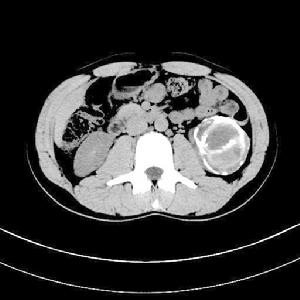

圖21例孤立性腎周圍膿腫,平掃顯示右腎向前外方移位,其內後方見大片液性低密度區,間以多數等密度粗大間隔,病變擴展至腎後旁間隙並累及背側肌群。增強掃描示膿腫間隔有中度增強,右腎功能低下(圖3)。

圖3 孤立性腎周圍膿腫。增強掃描右腎向前外後移位,其內後方巨大不規則液性低密度區,間以數個輕中度強化的間隔